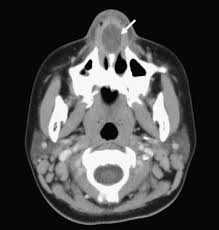

The nose is one of the most sensitive organs in the body. My doctor gave me mupirocin ointment, but it's not helping. Severe cases can lead to cellulitis as well as more serious and widespread infection. Doctors initial impression is nasal vestibulitis. And the nasal allergy is obviously relieved. Infants and toddlers often catch colds because they are just starting to build up their immunity to common viruses. In this article, learn more about the causes and treatments, plus when to see a nasal vestibulitis is an infection in the vestibule, or the entrance of the nose. Nasal vestibulitis is an infection of your nasal vestibule, which is the area just inside your nostrils. As this is a bacterial infection, treatment is done using antibiotics, such as dicloxacillin. Infection of the skin of the nasal vestibule is termed nasal vestibulitis. Minor infections at the opening of the nose, called nasal vestibulitis, may result in pimples at the base of nasal hairs (folliculitis) and sometimes crusts around the nostrils. In acute vestibulitis, the skin is red, swollen and tender. This inflammation disrupts the transmission of sensory information from the ear to the brain.

Nasal vestibulitis can be life threatening if ignored and not treated properly. Infection of the skin of the nasal vestibule is termed nasal vestibulitis. We'll go over the symptoms of nasal vestibulitis as well as warning signs you should. Nasal vestibulitis can occur as a primary infection or secondary infection, with risk factors including nasal hair plucking, nose blowing, nose picking, and nose piercing. In acute vestibulitis, the skin is red, swollen and tender.

Clinically, nasal vestibulitis is divided into chronic nasal vestibulitis and acute nasal vestibulitis. Kelenjar sebaceous folikel rambut vestibulum. In acute vestibulitis, the skin is red, swollen and tender. It s green in color as seen thru nasal endoscopy. A spray of rose geranium oil may ease nasal vestibulitis, which causes the lining of the nostrils to become excessively tender, bleed and form scabs. Nasal vestibulitis is a type of bacterial infection that affects the opening of the nose. Most cases are easy to treat, but more severe infections may require additional treatment to avoid complications. Vestibular neuritis and labyrinthitis are disorders resulting from an infection that inflames the inner ear or the nerves connecting the inner ear to the brain.